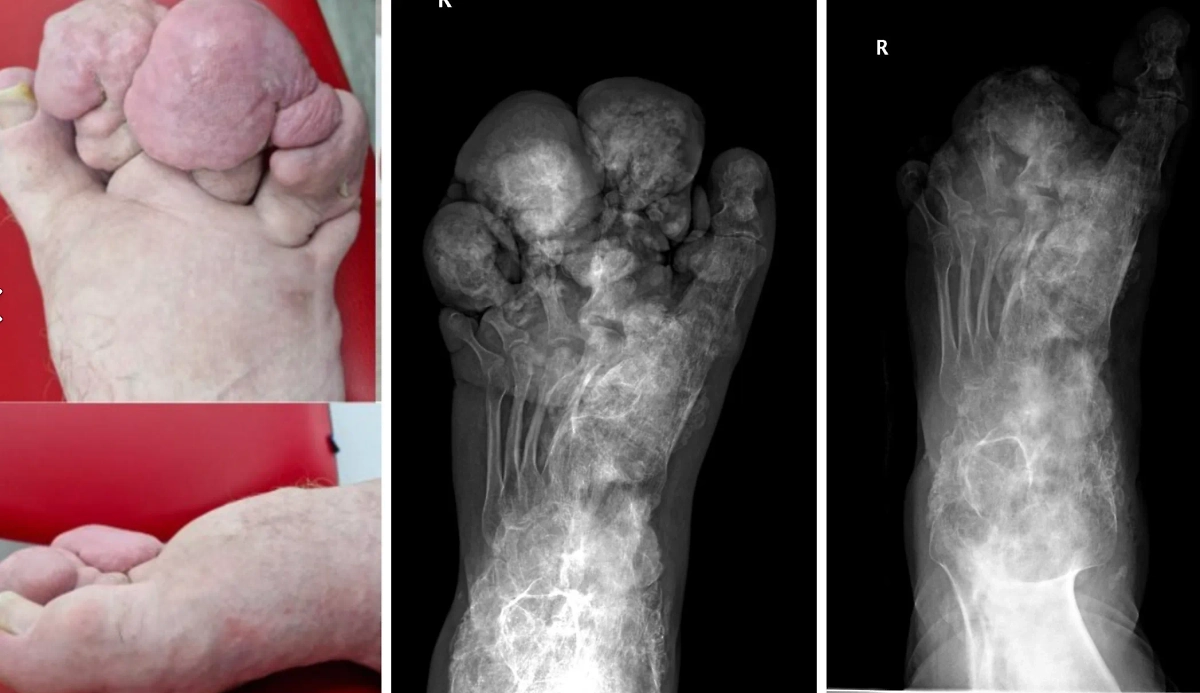

В Новосибирске врачи спасли 21-летнего пациента с редким заболеванием — синдромом Протея, вызывавшем чудовищные деформации тела. О проведённой операции рассказали в НИИТО им. Я.Л. Цивьяна. У Андрея Кочерыгина с детства деформировалось тело, он чувствовал жуткие боли и фактически перестал двигаться.

Впервые врачи заметили симптомы недуга у мальчика, когда ему было всего 9 месяцев. Но тогда Андрею не сразу смогли поставить точный диагноз, потому направляли его на лечебную физкультуру и массаж. Со временем на правой ноге начали образовываться патологические костные наросты — от стопы до бедра. Молодой человек стал испытывать сильные боли, а также стесняться своей внешности. Кроме того, у «человека-слона» были проблемы с выбором одежды, а обувь ему шили на заказ.

«Во время операции врачи удалили объёмные костные наросты и сформировали стопу, близкую к анатомически правильной форме. Вероятно, следующий этап хирургического лечения будет направлен на восстановление подвижности и правильной формы первого пальца стопы. Также рассматривается возможность эндопротезирования суставов с использованием стандартных или индивидуальных имплантатов», — рассказали в НИИТО.

Там добавили, что подобная болезнь возникает лишь у одного человека на миллион, при этом раньше недуг не поддавался лечению и человек утрачивал даже свои основные функции. Медики считают генетику основной причиной заболевания. Сейчас Андрей старается вернуться к полноценной жизни, он учится на инженера и увлекается картингом.